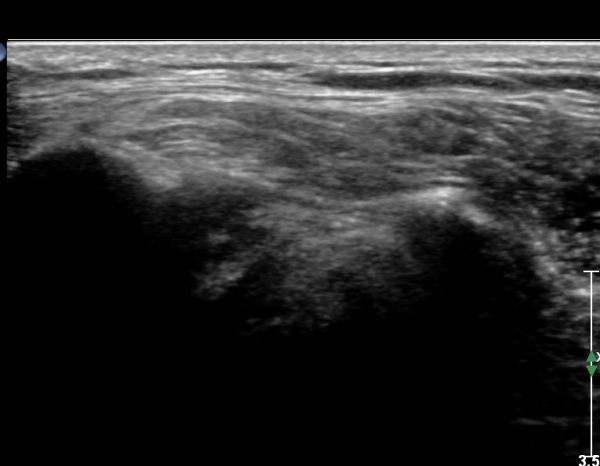

È¸Àü±Ù°³ Ⱦ´Ü¸é°Ë»ç¿¡¼­ ±Ø»ó°Ç ³»ÃøºÎ ºÎºÐ °á¼ÕÀÌ °üÂûµÇ°í(»çÁø 11) ŽÃËÀÚ¸¦ Á¶±Ý

¸»´ÜÀ¸·Î À̵¿ÇÏ´Ï ±Ø»ó°Ç ³»ÃøºÎ ÀüÃþÆÄ¿­ÀÌ °üÂûµÈ´Ù(»çÁö 12).